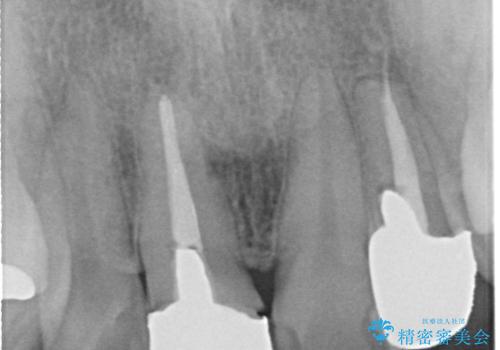

- 他院で装着された保険の前歯のかぶせ物が、他と歯と馴染まないので、自然な歯にしたいとのことで来院されました。

右上の1番目の歯の保険のかぶせ物と金属の土台を、ファイバーコアとオールセラミックにて再補綴する計画としました。

形態も色調もまわりの歯とは、調和がとれておらず、目立っていました。